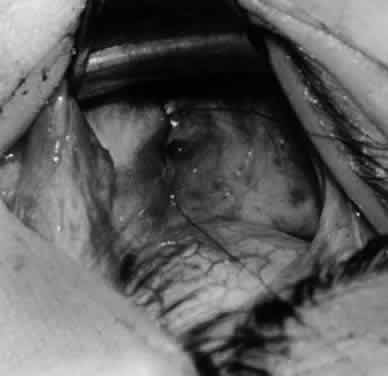

DENERVATION AND EXTIRPATION

The denervation procedure (Figs. 2132) allows the inferior oblique muscle to be released further into the operative field once the nerve has been sectioned (see Figs. 26 and 27). A 3-0 Vicryl suture ligature is placed around the inferior oblique muscle (see Fig. 28) as close to the Tenon's capsule penetration as possible. The inferior oblique is sectioned by cautery (see Fig. 29), just distal to the suture ligature. The cauterized stump is pushed through the opening in the Tenon's capsule (see Figs. 30 and 31) and a 6-0 or 7-0 Vicryl suture is used to close the opening, with either a running or a purse-string suture (see Fig. 32). The purse-string suture can be preplaced before the inferior oblique muscle is sectioned and closed after the muscle is sectioned. The advantage of the denervation and extirpation procedure is its ability to permanently correct 4+ overaction of the inferior oblique.10,18 In addition, it is the best operative procedure to eliminate recurring inferior oblique overaction after disinsertion, myectomy, or recession.10 Disadvantages include permanent underaction of the inferior oblique muscle in some patients. Pupil dilation can occur but the dilation usually is transient, clearing in 3 to 6 months.10,18

Fig. 21. A hemostat is placed adjacent to the insertion of the right inferior oblique muscle.

Fig. 22. An Aebli scissor is used to section the inferior oblique muscle from the globe.

Fig. 23. The inferior oblique muscle is drawn into the operative field with a hemostat. This step may be used for the recession procedure if the surgeon is concerned about the placement of the 6-0 Vicryl suture while the muscle is attached to the globe in the proximity of the macula. The recession sequence would follow after the placement of the suture while the muscle is grasped in the hemostat.

Fig. 24. The eyelid speculum is removed and a Desmarres lid retractor is placed inferiorly. The inferior oblique muscle is drawn superiorly and nasally. The fusiform expansion of the inferior oblique muscle is evident on the posterior border, where the nerve to the inferior oblique muscle and artery and vein enter the inferior oblique muscle. The Stevens muscle hook is used to hook the neurovascular bundle.

Fig. 25. The hook is advanced further for identification of the neurovascular bundle on the inferior oblique muscle.

Fig. 26. Cautery is applied to sever the neurovascular bundle, and a sponge is used to protect the sclera and lids from cautery.

Fig. 27. As the neurovascular bundle is severed completely, the inferior oblique muscle will be released of the normal tension provided by the neurovascular bundle on the posterior border of the inferior oblique muscle.

Fig. 28. The inferior oblique muscle is drawn further into the operative field, and a 3-0 Vicryl suture ligature is applied about the belly of the muscle.

Fig. 29. Cautery is used to sever the inferior oblique muscle and to provide hemostasis.

Fig. 30. The stump of muscle is placed through the Tenon's capsule opening. The surgeon must apply sufficient cautery to prevent postoperative bleeding.

Fig. 31. The inferior oblique muscle stump is visible at the opening in the Tenon's capsule before closure with 6-0 or 7-0 Vicryl suture. The S-28 half-circle curved needle is preferred to the S-29 needle, which has a 3–8-circle curve.

Fig. 32. The Tenon's capsule opening is closed with 6-0 or 7-0 Vicryl suture to place the inferior oblique muscle entirely outside Tenon's capsule.